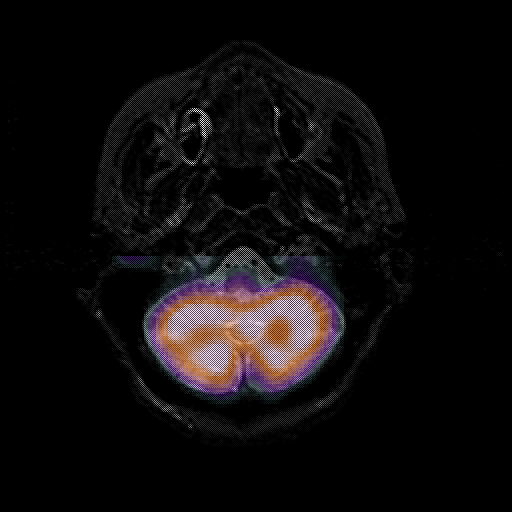

overlay 1: Slice 9

Slice 9

MRCBFCBF with

T1PDT2T1PDT2